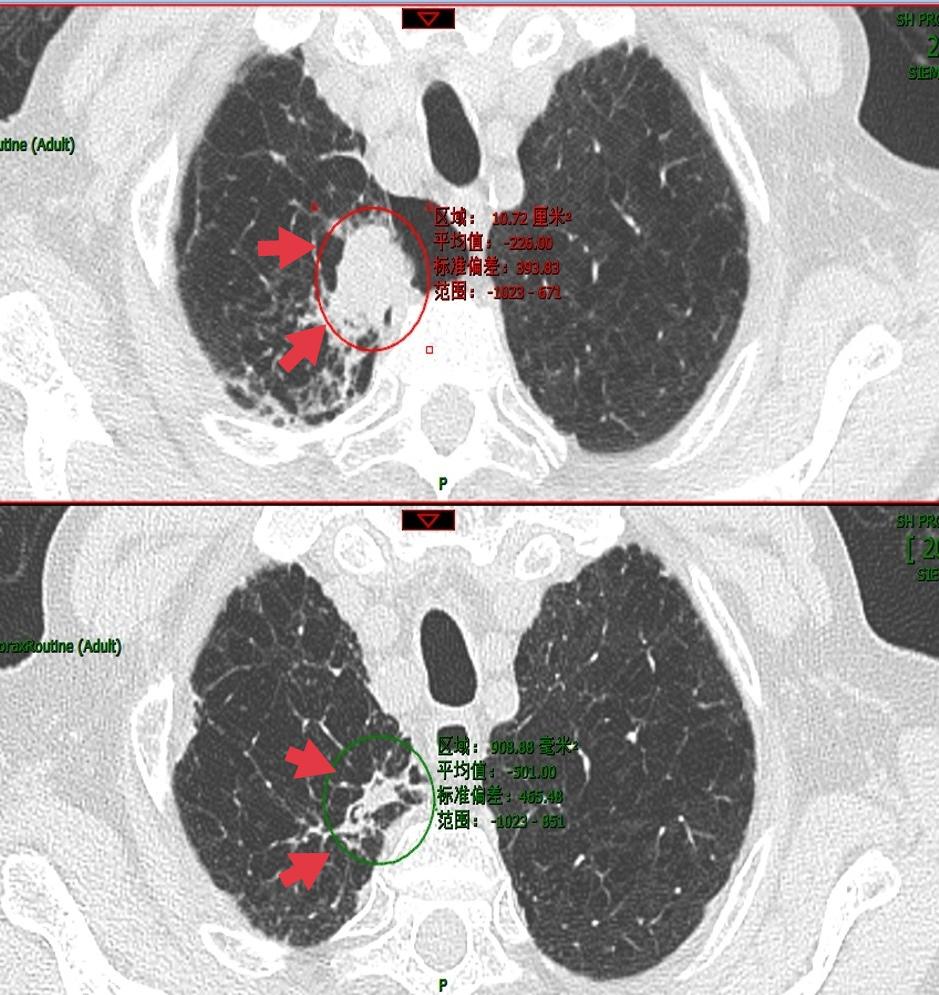

重度肺气肿患者,发现右上肺肺结节一个月。一个月后复查即有增大。肺气肿患者,肺结节形态不典型,但疑似肿瘤。

患者经过质子重离子医院的精准治疗后,三个月复查,肿瘤明显缩小,仅遗留少许纤维灶,达到根治效果。效果很惊艳。而且没有任何放射性肺炎的并发症。